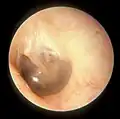

Examination

When the eardrum is illuminated during a medical examination, a cone of light radiates from the tip of the malleus to the periphery in the anteroinferior quadrant, this is what is known clinically as 5 o'clock.